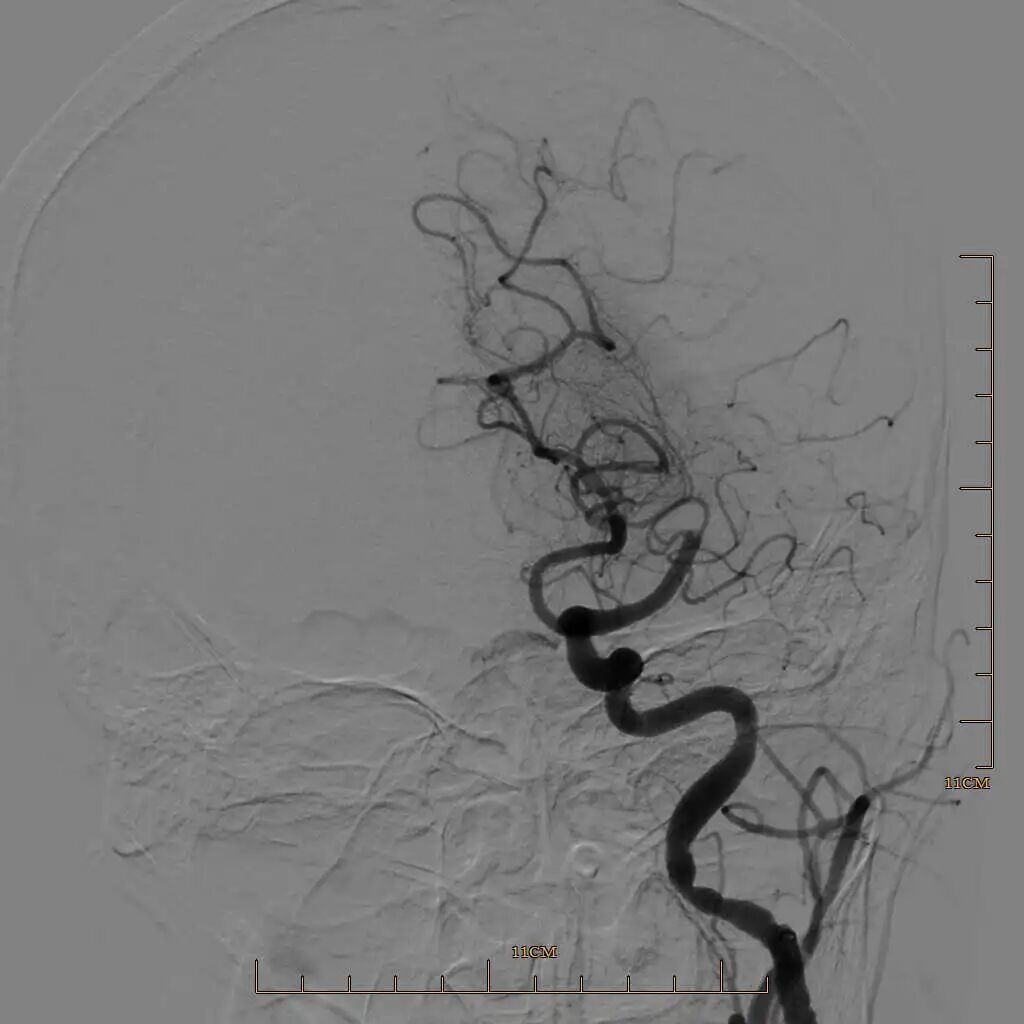

90cm Locaste 088输送导管建立路径,造影提示左侧大脑中动脉M1段闭塞。

Tarvos微导丝携微导管超选大脑中下干M2末端。

取栓后下干再通,上干仍闭塞。

Tarvos微导丝携微导管超选大脑中上干,微导管冒烟确认血管真腔,释放取栓支架。

半回收取栓支架取栓后大脑中动脉上干血管再通。